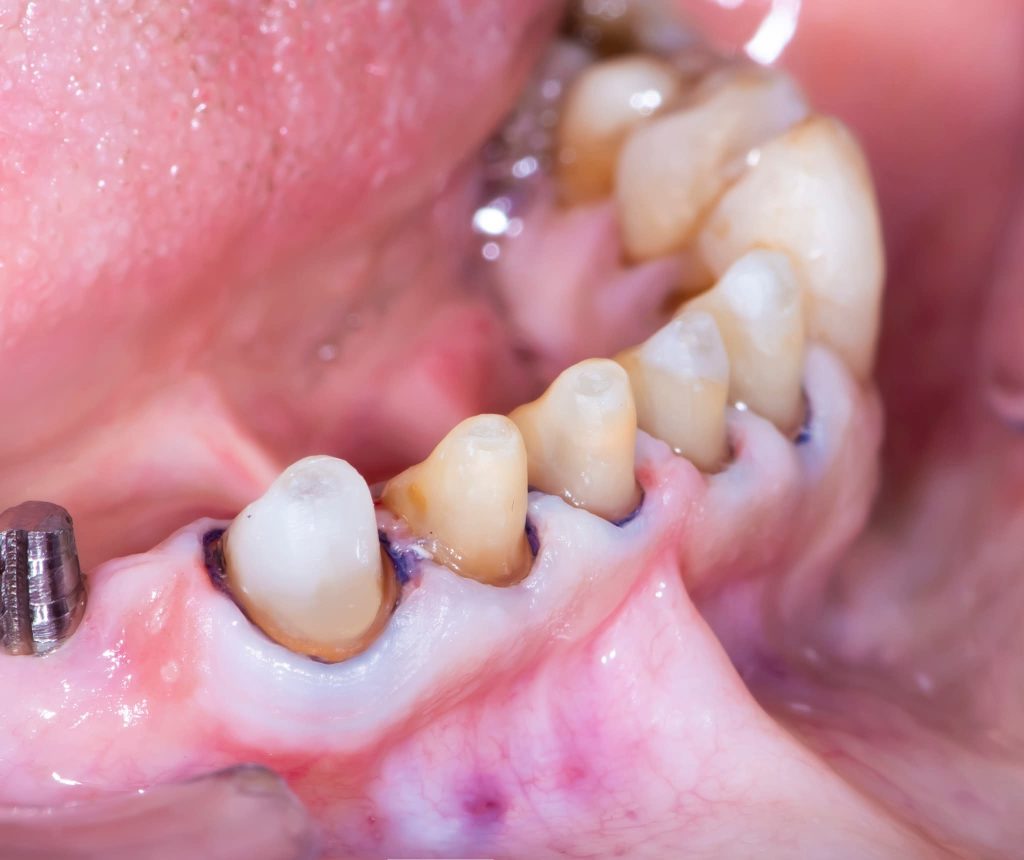

I am revisiting this Full Mouth Rehabilitation case, which was my first published case in this group.

2. Corrective Phase:

This phase included all necessary corrective procedures:

Extraction of hopeless teeth.

Endodontic treatments.

Replacement of old, defective fillings.

Tooth build-ups to the new vertical dimension of occlusion, aided by the silicone indices.

Removable prostheses were inserted, and the patient was monitored for one month.

Minor occlusal adjustments were made during this period to achieve a more stable, comfortable occlusion and proper phonetics.